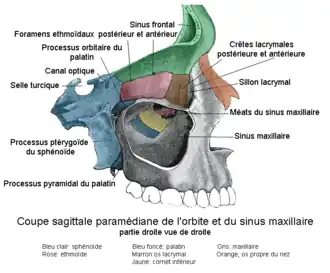

Il se compose d'un corps creusé d'un sinus maxillaire et d'un processus frontal.

- un sinus, le sinus maxillaire, en relation avec le nez.

- la face supérieure, ou orbitaire, qui compose la paroi inférieure de la cavité orbitaire.

- la face médiale qui contient le hiatus

Le sinus maxillaire

Il s'agit d'une cavité pneumatique en relation avec la cavité nasale, son volume varie en fonction de l'âge et des individus. Les dents qui sont en regard de cette cavité sont appelées « dents antrales ».

Coupe sagittale para-médiane

Coupe sagittale para-médiane Les os du crâne